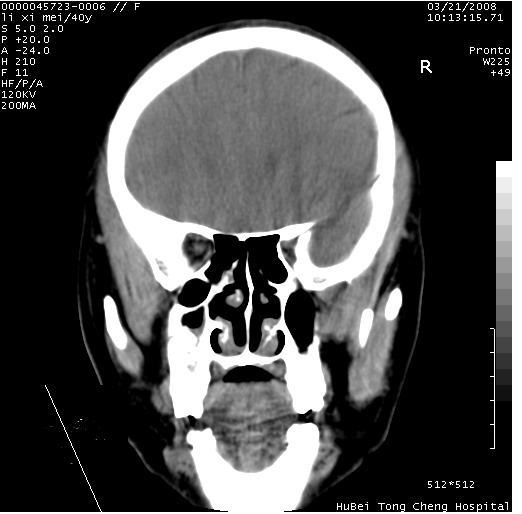

以下是引用卜一在2008-3-21 20:18:00的发言:[br]双侧上颌窦炎症,双下鼻甲肥大!不除外霉菌感染!

以下是引用qiuleiyu在2008-3-21 21:46:00的发言:[br]支持;上颌窦炎,窦内高密度影,建议横断位观察与上颌窦前壁关系。除外骨源性病变。